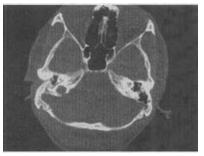

- 单项选择题 男,23岁,右耳流脓十余年,右外耳道流脓,鼓膜穿孔,CT检查如图,最可能的诊断是()。

A、慢性中耳乳突炎

- A